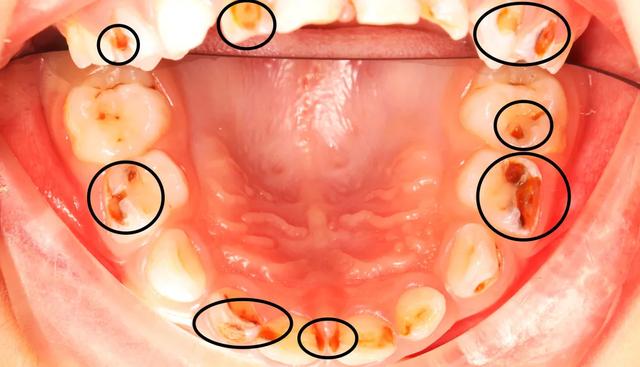

△密密麻麻的小黑牙和洞洞△

童童乳牙蛀了17颗,任其发展下去,势必影响恒牙的萌出,还可能导致营养不良。

但要说治吧,童童连张嘴检查都这么费劲,龋齿有17颗可怎么治啊……霸王硬上弓,娃心里肯定会留下阴影,万一因为反应太大造成意外伤害,就更麻烦了。